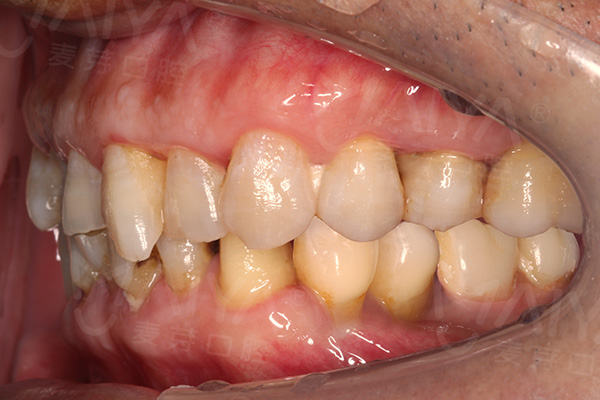

陈老伯种牙后口内照